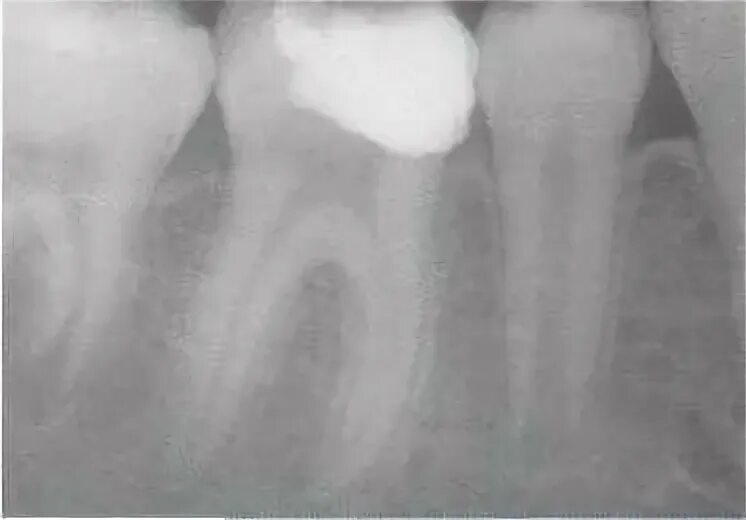

Лечение пульпита с несформированными